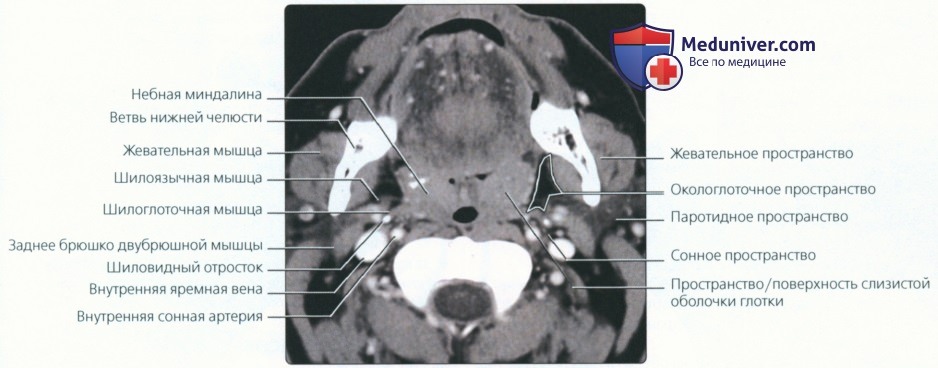

Анатомия межплеврального пространства